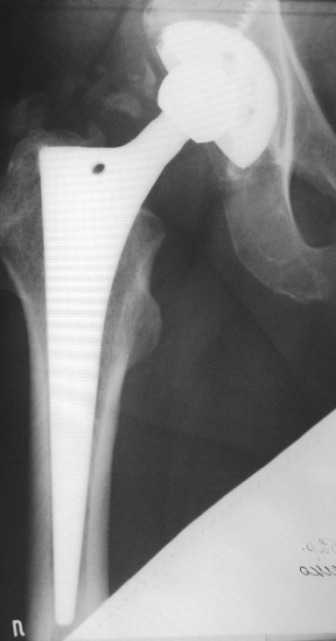

Здравствуйте уважаемые коллеги! Хочу попросить совета по следующему случаю.

Больной 1952 г.р. тотальное эндопротезирование обеих т/б суставов. Правый 2004г., левый в 2007г.

19.01.09. стали беспокоить боли в средней трети левого бедра по

наружной поверхности. Боли беспокоят только при ходьбе. Лежа и сидя

болей нет. Стоя вертикально, перенеся массу тела на правую ногу боль

исчезает, при равномерном распределении нагрузки снова появляется.

Снимки прилагаю.